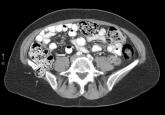

Spontaneous Retroperitoneal Hematoma

Incisional Iliac Hernia